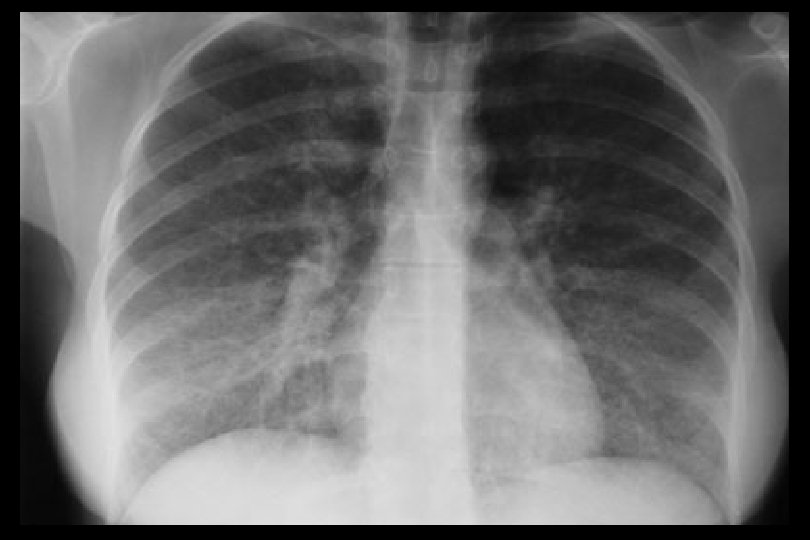

Tempo di comparsa anche superiore a 12 mesi 43 casi descritti in letteratura dal 2000 al 2004 (Pham et al, Transplantation 77, 2004) Dose dipendente? Sintomi Dispnea da sforzo Tosse secca Febbre (50%) Dimagramento Emottisi Strumentali Rx Torace: addensamenti bilaterali Vetro smerigliato TC: Infiltrati alveolo interstiziali Broncoscopia: Alveolite linfocitaria Emorragia polmonare Biopsia: Polmonite organizzata Bronchiolite obliterante